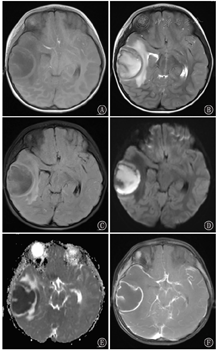

BA MRI典型表现为T1低信号,T2高信号,DWI高信号,ADC低信号,T1动态增强扫描呈环形强化,周围脑组织水肿明显(图1)。47例患儿中,单发型BA 24例(51.1%),多房型BA 9例(19.1%),多发型BA 14例(29.8%)(图2A,图2B,图2C)。根据增强MRI上脓肿壁厚度分类,薄壁组(壁厚<2 mm)28例(59.6%),厚壁组(壁厚≥2 mm)19例(40.4%)(图2D、图2E)。脓肿体积≤4 cm者27例(57.4%),>4 cm者20例(42.6%)。根据脓肿所在位置分类,位于脑深部/功能区(丘脑、基底核、中央区等)15例(31.9%),位于脑浅表部位/非功能区32例(68.1%)。

注:MRI:磁共振成像 MRI:magnetic resonance imaging